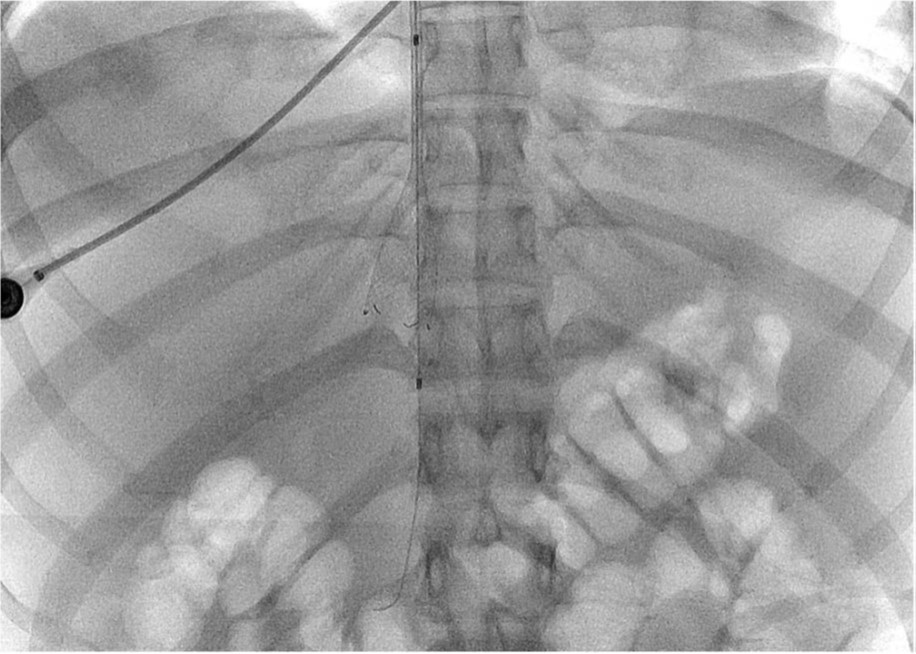

Fig. 2. C

C. Radiography obtained during aspiration thrombectomy of IVC thrombus by renal guiding catheter.